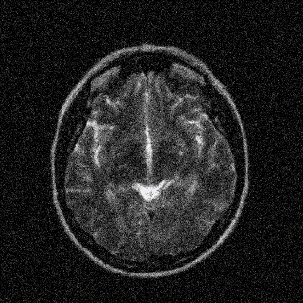

Figure 8: Reconstruction results for 25% cartesian sampling. (a) Original. (b)-(h) Reconstructed images. (i)-(n) The errors of six CSMRI methods.

As shown in Figs. 7, 8 and 9, Sparse MRI and DLMRI have a lot of unpleasant artifacts, Residual learning and U-net can eliminate most of artifacts, but are not ideal for restoring image details. However, the proposed method can reconstruct better MR images, which outperforms other competitive methods in visualization of structures reconstruction and artifacts removal. Meanwhile, we can see from the absolute error residuals for three sampling experiments that the proposed MDN algorithm restores a finer detail structure than other algorithms. Moreover, we present the PSNR and SSIM values in Table I for different algorithms, sampling masks and sampling rates. It is demonstrated that the proposed method provides better reconstruction performance and visual results than other competitive methods. We can also see the obvious improvement of all algorithms over zero-filling both in visualization. In particular, a higher SSIM value of Sparse MRI appears when using 30% variable density random sampling, however, Sparse MRI generates more artifacts than the proposed MDN.